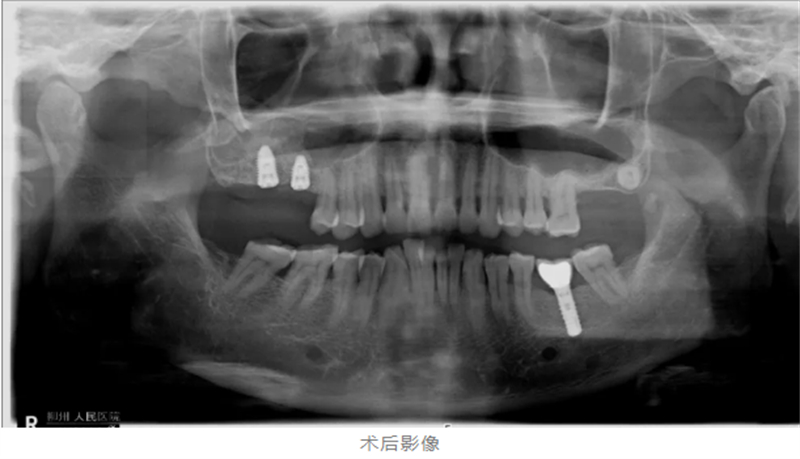

口腔科種植團隊為黃阿姨進行了全面檢查,影像學結果顯示,其雙側(cè)上頜后牙區(qū)牙槽骨吸收嚴重——左側(cè)牙槽骨厚度僅1.6mm,右側(cè)也僅約3mm,遠不能滿足常規(guī)種植牙植入所需骨量。

在局麻狀態(tài)下,手術團隊通過側(cè)壁開窗,提升竇底黏膜,植入骨粉,成功將骨厚度增至7-8mm,為種植體穩(wěn)定性奠定了堅實基礎。